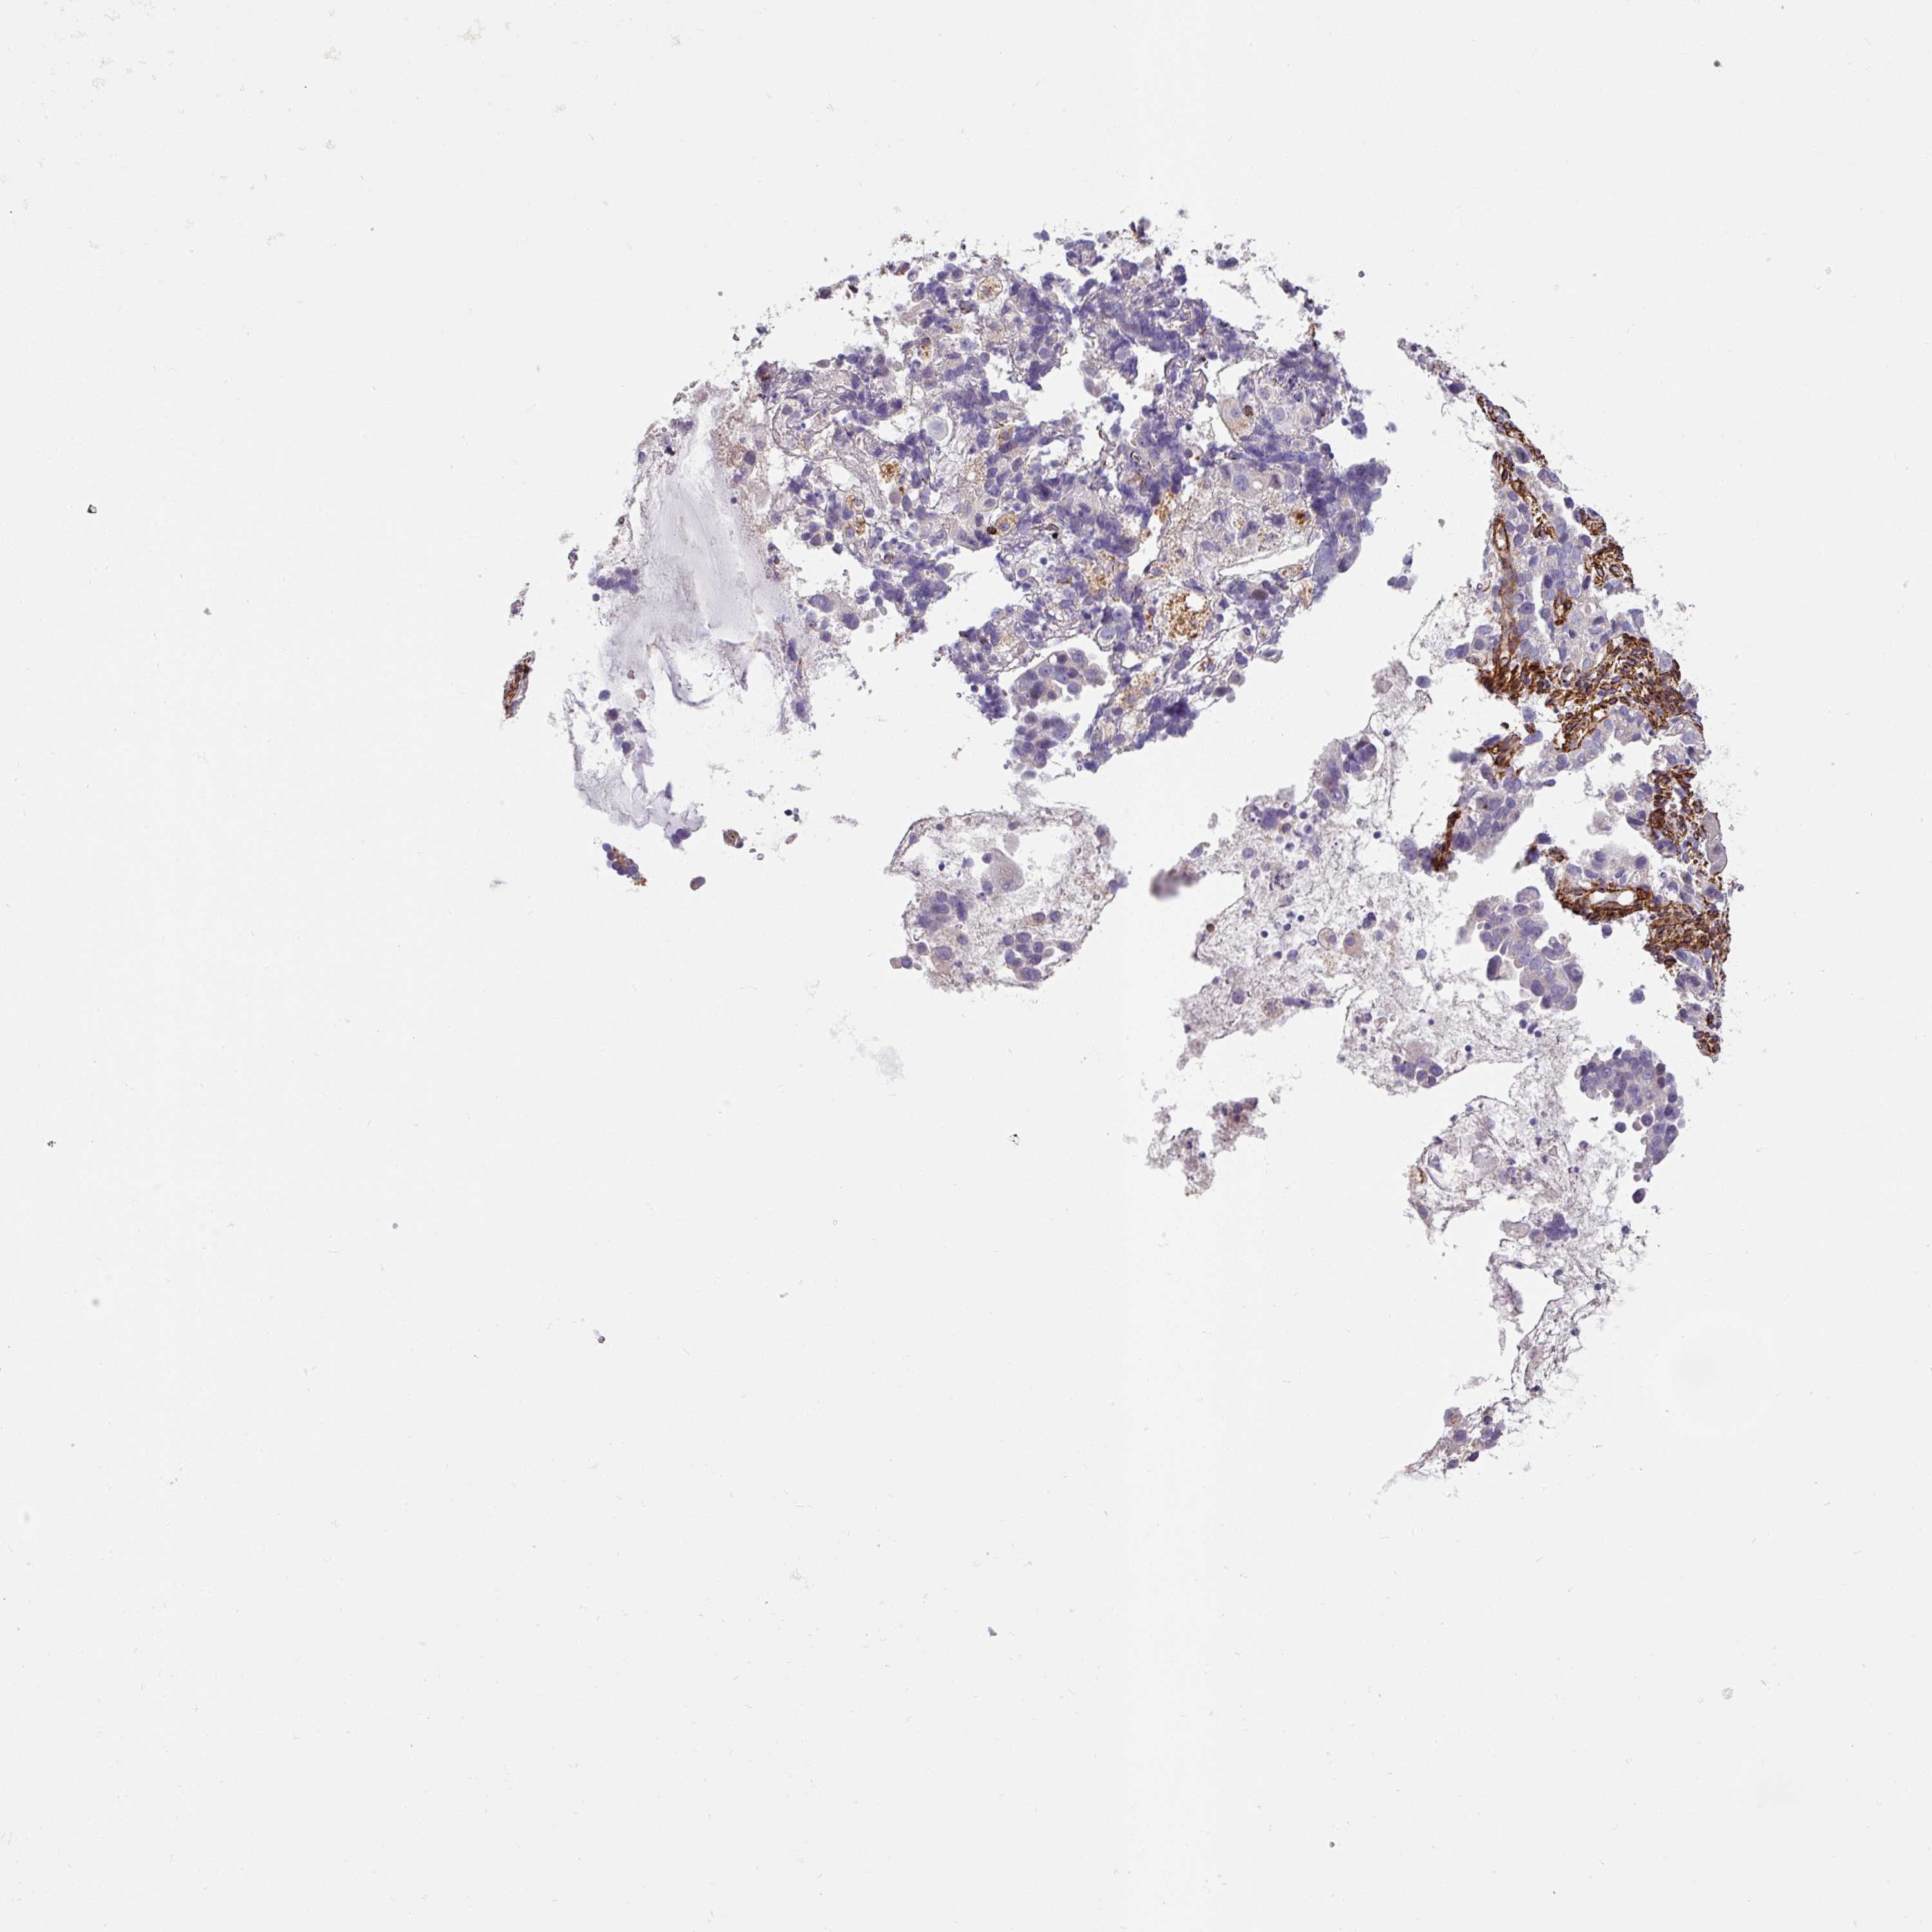

ENDOMETRIAL CANCER - Protein expressioni

A mouse-over function shows sample information and annotation data. Click on an image to view it in a full screen mode. Samples can be filtered based on level of antibody staining by selecting one or several of the following categories: high, medium, low and not detected. The assay and annotation is described here.

Note that samples used for immunohistochemistry by the Human Protein Atlas do not correspond to samples in the TCGA dataset.

Antibody stainingi

Antibody staining in the annotated cell types in the current human tissue is reported as not detected, low, medium, or high, based on conventional immunohistochemistry profiling in selected tissues. This score is based on the combination of the staining intensity and fraction of stained cells.

Each image is clickable and will lead to virtual microscopy that enables deeper exploration of all samples and also displays staining intensity scores, fraction scores and subcellular localization as well as patient and tissue information for each sample.

Antibody HPA052708

Staining

High

Medium

Low

Not detected

Intensity

Strong

Moderate

Weak

Negative

Quantity

>75%

75%-25%

<25%

None

Location

Nuclear

Cytoplasmic/membranous

Cytoplasmic/membranous,nuclear

Adenocarcinoma, NOS

Carcinoma, NOS